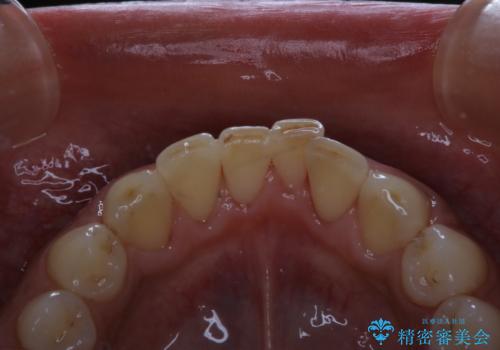

- 毎日コーヒーを飲むため、歯の着色がとっても気になるとのことでした。歯科でのクリーニングは2.3年ぶりのため全体的にきれいにしてほしいとのことでした。

PMTC60分コースを行いました。

PMTC(保険外治療)は、毎日の歯磨きで落としきれない汚れや、コーヒ、紅茶・タバコのヤニなどの着色も除去します。目には見えない歯と歯の間・歯肉の境目・インビザライン中はアタッチメント周囲などに残っているプラーク(歯垢)もしっかり取り除きます。PMTCでは専門的な機械や材料を使用して、徹底的に汚れを除去するため、虫歯・歯周病・口臭予防などにつながります。

またPMTCを行うことで、ご自身本来の歯の色になり自然な明るさになります。